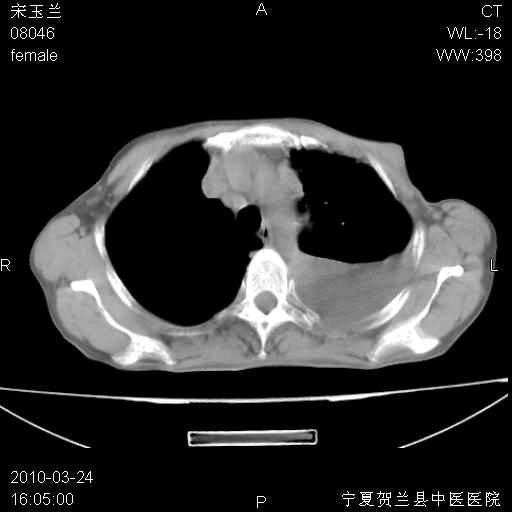

以下是引用zxl51642在2010-3-24 18:49:00的发言:[br]结合乳腺癌术后病史,考虑双肺及纵隔淋巴结多发转移、左侧胸膜转移并左侧大量胸水、左下肺膨胀不全。